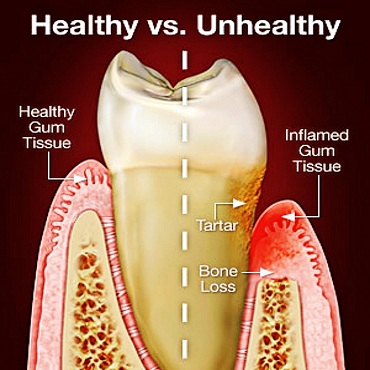

Shagun Dental Care in Lucknow offers a host of treatments and cures for a wide range of dental ailments faced by the patients. Few of the dental procedures they offer range from inducing fillings and repairs in the tooth, undertaking root canal surgeries, applying crowns (caps), bridges and implants, teeth whitening as well as extractions (surgical removal) of cavities/milky /disfigured/wisdom teeth.

Our approach allows to identify the underlying causes that are acting as obstacles which must be addressed before treatment can be achieved.